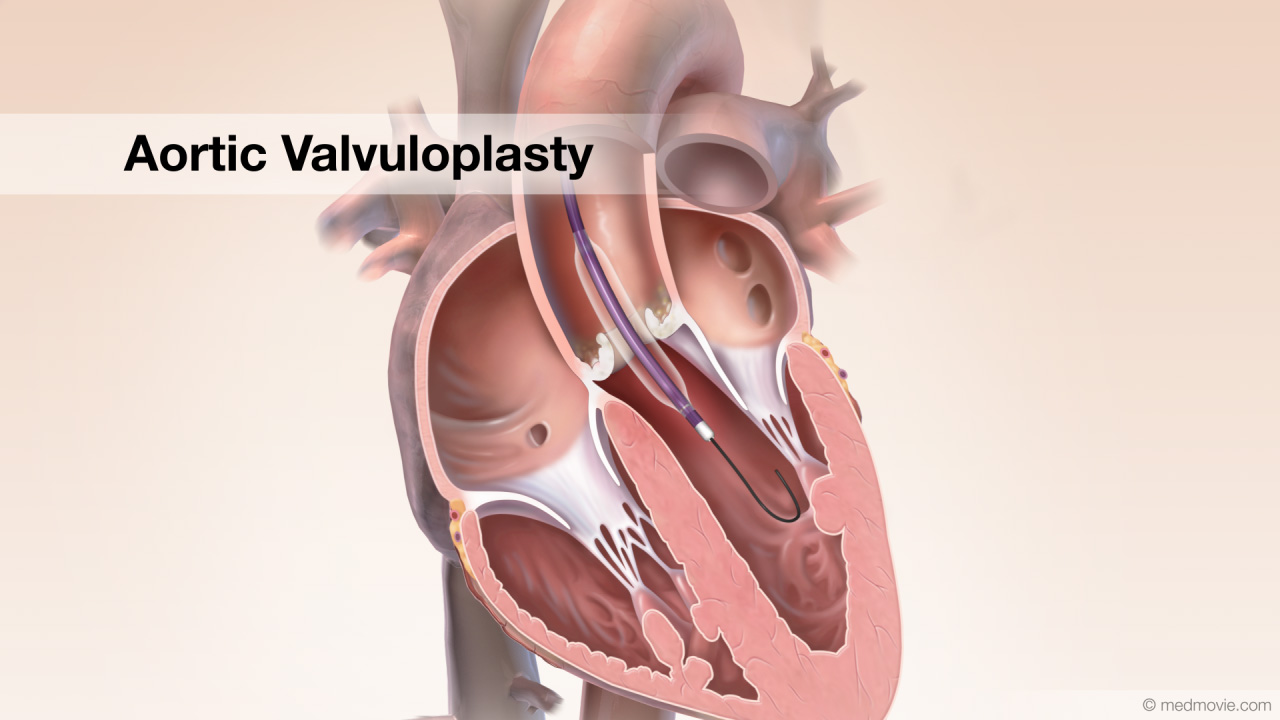

Пороки сердечно-сосудистой системы: виды и признаки